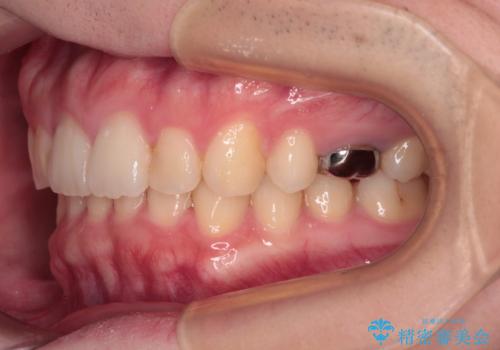

インビザラインによる矯正治療と奥歯のインプラント治療

- 咬み合わせと前歯のデコボコを気にして来院された患者様です。

前から5番目の永久歯が3本欠損しており、乳歯が残存している状態でしたが、インビザラインでも十分に対応可能と判断し、インビザラインにて矯正治療を行うこととしました。

右下の残存している乳歯は萌出しきれておらず、全く咬み合っていない状態であり、インビザラインにて移動できない可能性があるため、ワイヤー矯正の併用も念頭に置いて治療を開始しました。

今回は部分的にワイヤー矯正を用いましたが、右下の乳歯は全く動かなかったため、抜歯をした上でインプラントを埋入し、オールセラミッククラウンにて補綴治療を行いました。